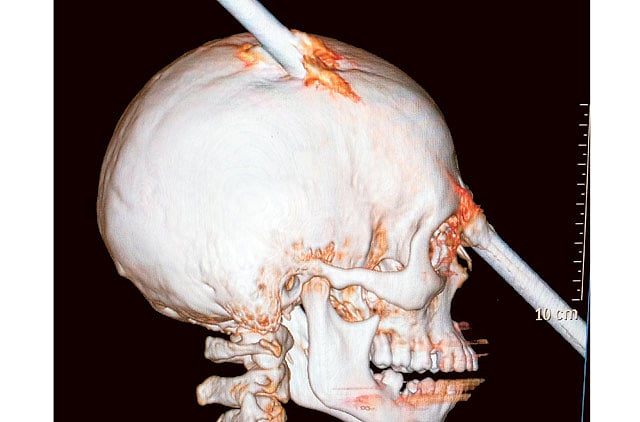

Rio de Janeiro: A 24-year-old construction worker survived after a 6-foot metal bar fell from above and pierced his head, doctors said on Friday.

Luiz Alexandre Essinger, chief of staff at Rio de Janeiro’s Miguel Couto Hospital, said doctors successfully withdrew the iron bar from Eduardo Leite’s skull during a five-hour surgery.

“He was taken to the operating room, his skull was opened, they examined the brain and the surgeon decided to pull the metal bar out from the front in the same direction it entered the brain.” Essinger said.

The bar fell from the fifth floor of a building under construction, went through Leite’s hard hat, entered the back of his skull and exited between his eyes, Essinger said, adding It really was a miracle that Leite survived.

Ruy Monteiro, the hospital’s head of neurosurgery, told the Globo TV network that Leite escaped by just a few centimetres from losing one eye and becoming paralysed on the left side of his body.

He said the bar entered a “non-eloquent” area of the brain, an area that doesn’t have a specific, major known function.